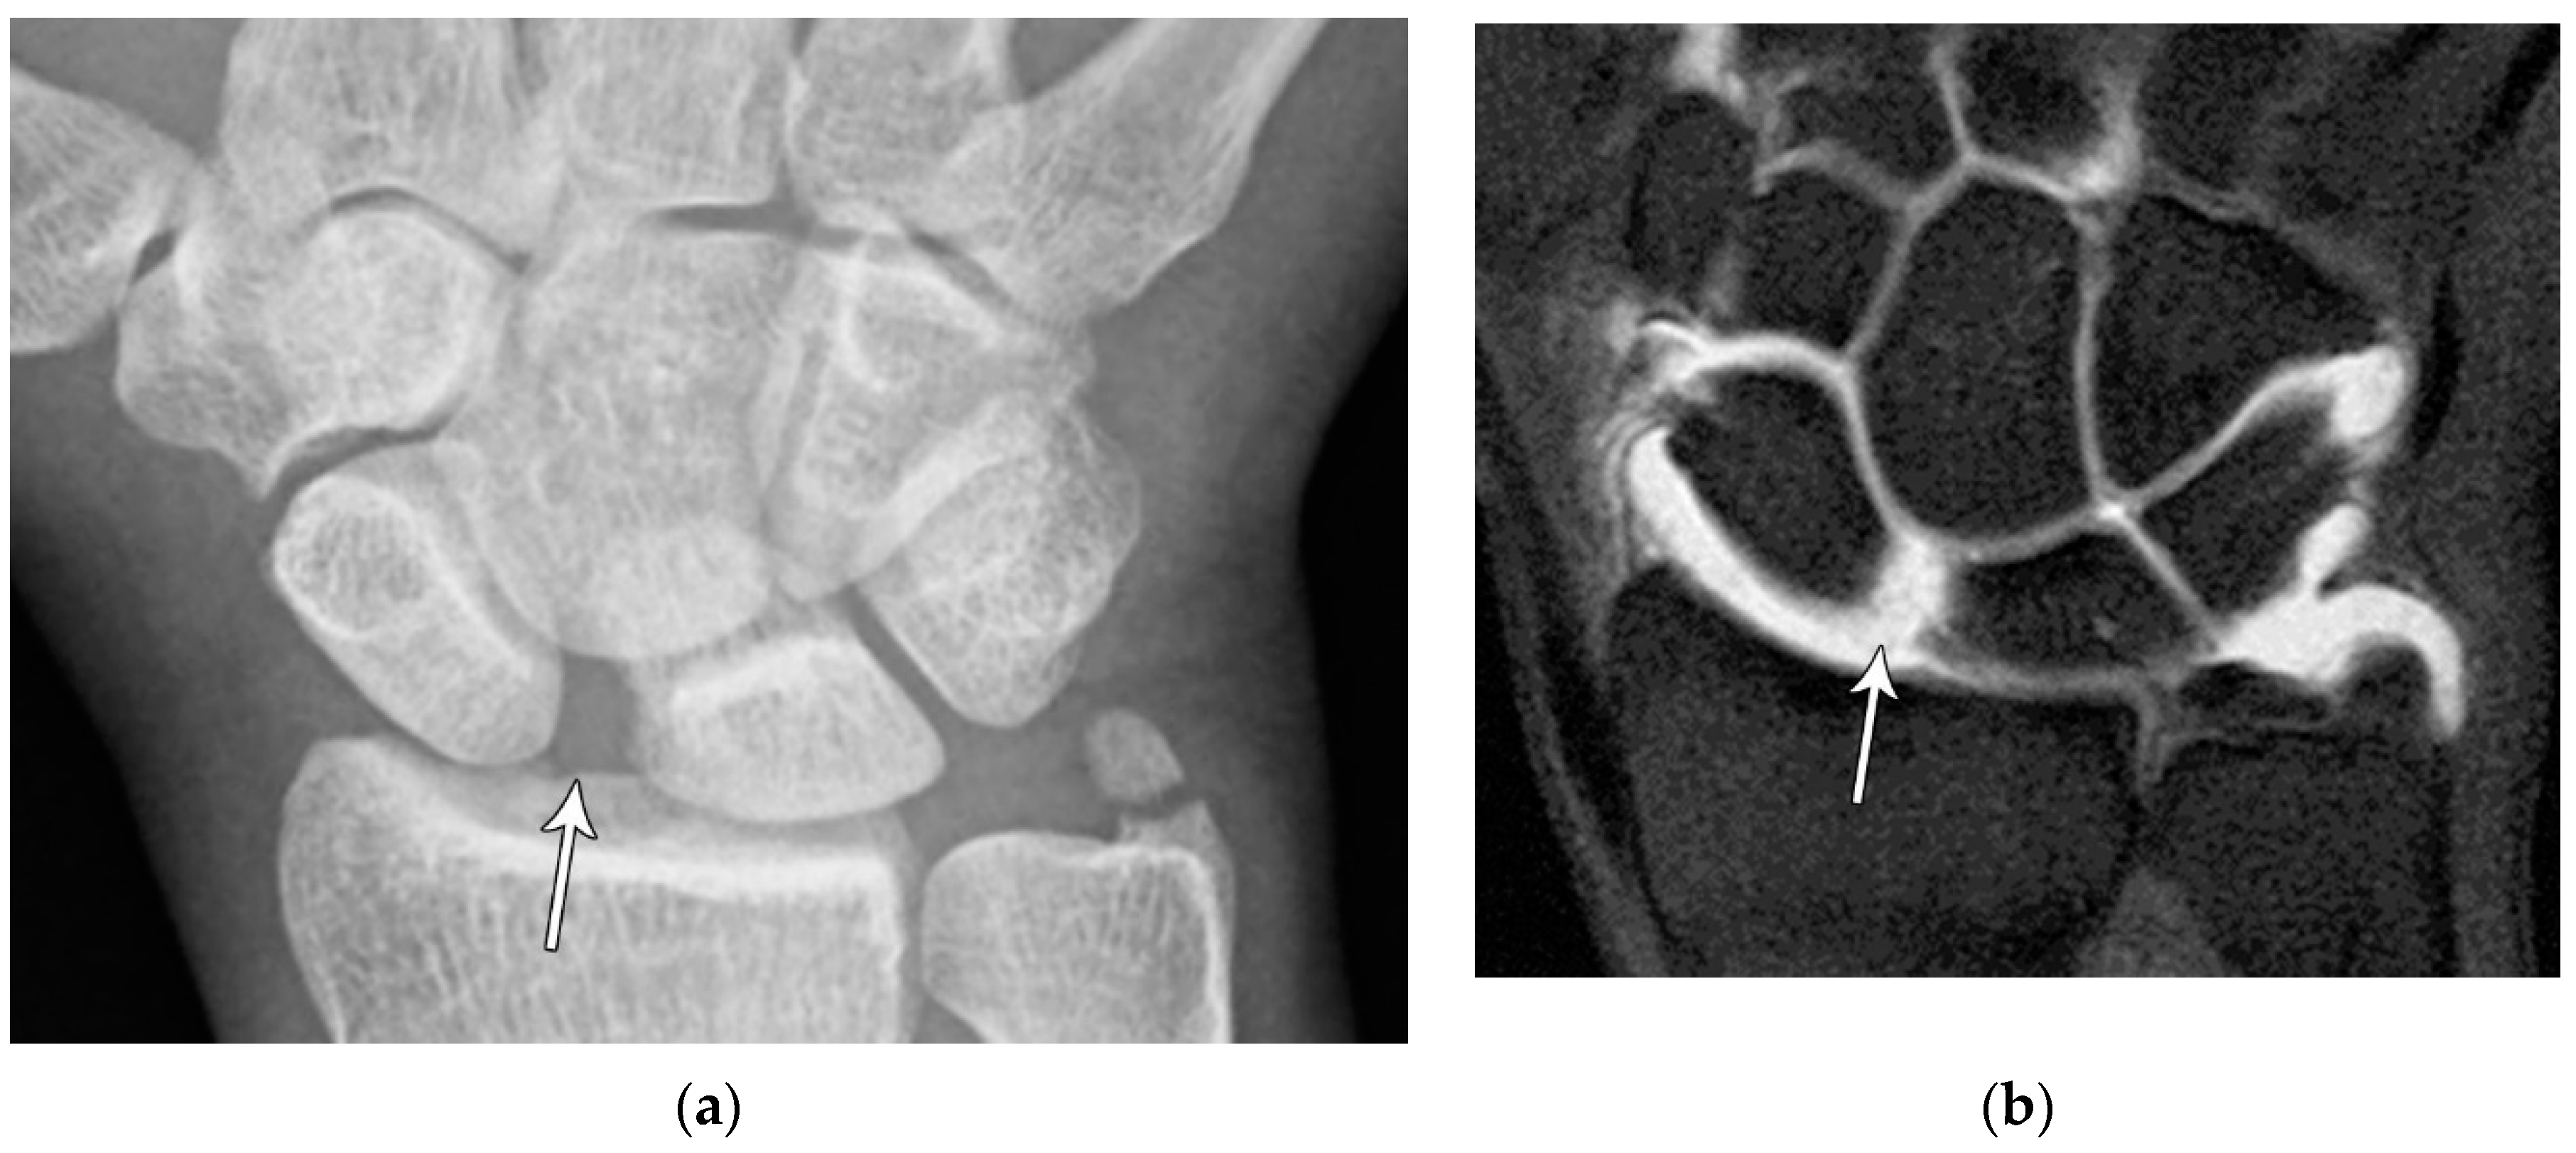

Common scaphoid fracture complications include avascular necrosis and nonunion [10]. Avascular necrosis is a dreaded outcome resulting from loss of the proximal arterial supply due to the distal entry point of nutrient vessels. This retrograde perfusion of the proximal pole makes it vulnerable to losing its vascular supply when fractured. Sclerosis of the proximal pole indicates osteonecrosis (Figure 5). With scaphoid nonunion, biomechanical alterations contribute to rapidly progressive degenerative arthritis and instability referred to as scaphoid nonunion advanced collapse (SNAC) [16]. Nonunion occurs in 5-10% of cases and has a higher incidence with displaced fractures (Figure 6). During wrist extension, the distal scaphoid fragment rotates into flexion while the proximal scaphoid fragment extends with the lunate. The resultant abnormal contact between the distal fragment and radius begins the first stage in degenerative collapse. This progresses into the second stage as scaphocapitate osteoarthritis develops and finally to the third stage with progression to capitolunate osteoarthritis and proximal radial migration of the capitate dorsal to the lunate. Treatment of SNAC wrists, depending on the degree and severity of the osteoarthritic collapse include scaphoidectomy with four-corner arthrodesis or wrist fusion [17]. Four-corner fusion helps reduce joint pain while maintaining some range of motion, as opposed to total wrist fusion (Figure 7).

Figure 5. (a) PA radiograph showing marked sclerosis (arrow) of the proximal pole of the scaphoid after a scaphoid fracture. (b) Coronal reformatted CT in a different patient showing sclerosis (arrow) of the proximal pole of the scaphoid after a scaphoid fracture, indicating osteonecrosis.